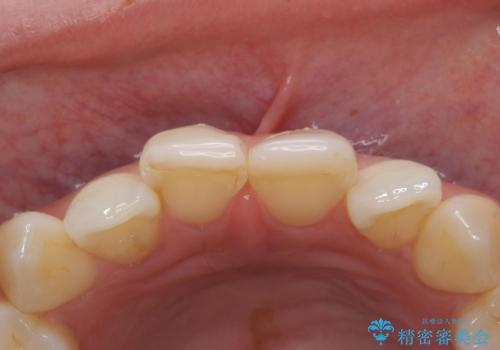

前歯には審美性も適合も良いクラウンを装着。

歯ぐきの状態も非常に良いです。

歯のがたつきも改善され、大変喜んでいただけました。